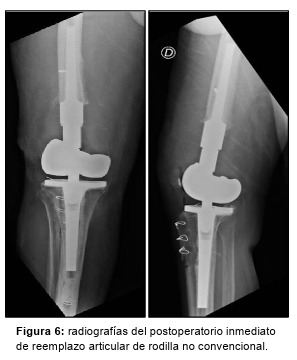

Los cultivos tomados se informan 5/5 negativos; continúa con ciprofloxacina + rifampicina por 9 semanas y se programa la cirugía definitiva de reemplazo articular de rodilla no convencional (Figura 6). Luego de 6 semanas, se realiza el 2do tiempo.

Abordaje parapatelar interno sobre cicatriz previa. Se realiza osteotomía de la tuberosidad anterior de la tibia (TAT). Se retiran el espaciador y placa previos. Se realizan osteotomías en tibia proximal y fémur distal respectivamente. Luego se prueba la estabilidad de los componentes en flexo-extensión de manera satisfactoria por lo que se cementan los implantes definitivos en dos tiempos.

Se repara la TAT con cerclaje de alambre. Se coloca drenaje hemosuctor subfascia y finalmente se cierra por planos.